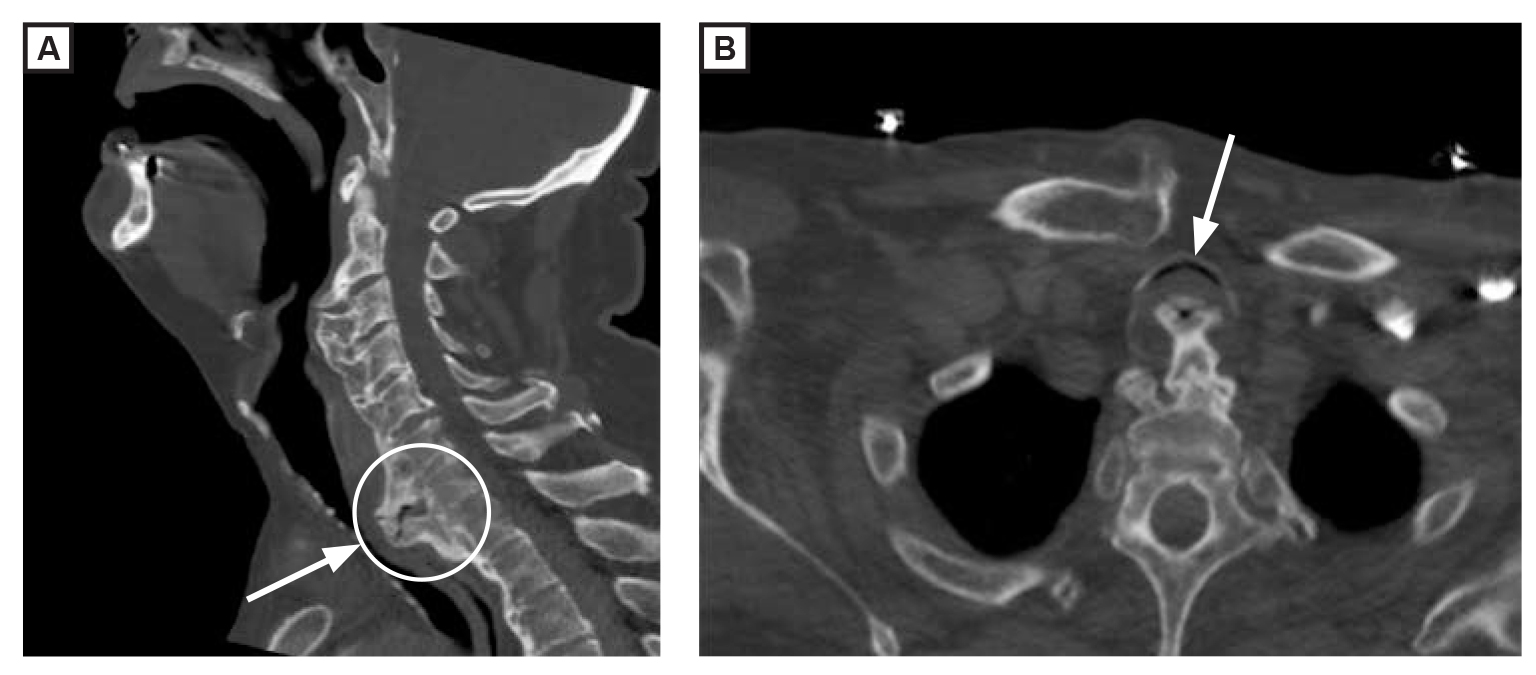

A 74-year-old man with a history of diabetes mellitus and hypertension was found unresponsive in his home. The patient arrived at the emergency department after having cardiac arrest in the ambulance. He was admitted to the intensive care unit and ventilation was discontinued on hospital day 2. A positional stridor, hypoxia, and dysphagia were noticed after extubation. A computed tomographic image of the cervical spine showed anterior hyperostosis that was most prominent at C6-7 (image A, circle), which caused marked extrinsic compression of the esophagus and posterior trachea (image A and image B, arrows). An osteophyte excision was performed on day 10. The patient was able to maintain his own airway; however, dysphagia persisted and a percutaneous endoscopic gastrostomy tube was placed on day 15. On day 20, the patient was discharged to inpatient rehabilitation. Two months later, the tube was removed.

Diffuse idiopathic skeletal hyperostosis (DISH) is a rheumatologic disorder, with primary clinical features being rigidity of the spine and advanced age.1 In severe cases, DISH can cause dysphagia and stridor.2 Classification criteria for identifying DISH include calcification and ossification along the anterolateral aspect of at least 4 contiguous vertebrae, preservation of the spaces between the intervertebral disks, and absence of facet joint ankylosis or sacroiliac joint erosion.3 Treatment depends on the symptoms.